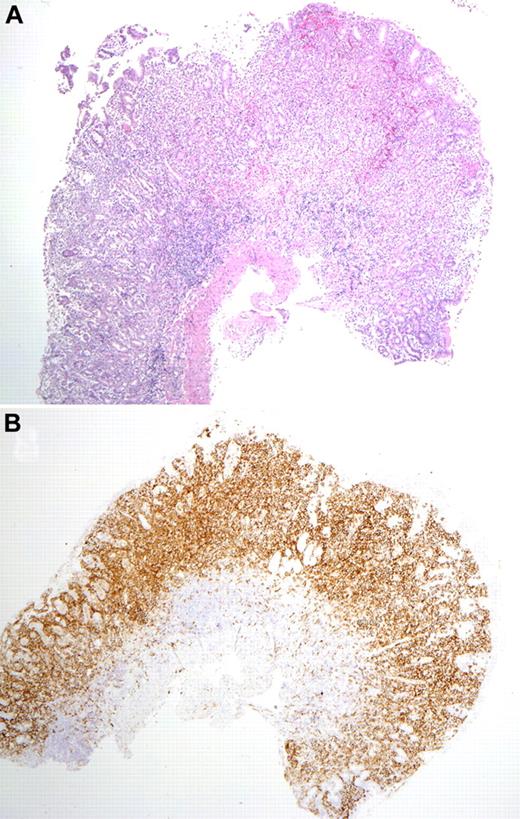

Mucosal biopsy findings. (A) Biopsy of the gastric antrum shows diffuse infiltration of the lamina propria by the atypical cells. The muscularis mucosa is intact, without infiltration of the submucosa. (B) A CD56 stain of the same biopsy highlights the atypical infiltrate. Photomicrographic images were acquired with a Nikon Eclipse 50i microscope equipped with an Olympus DP71 camera and software. Final image preparation was performed with Adobe Photoshop CS3 extended Version 10.0.1. Magnification: 2×/0.1 NA Plan Apo lens.

The gastrointestinal biopsies showed similar morphologic features among all patients. There was expansion of the lamina propria by a relatively well-circumscribed but confluent infiltrate of intermediate to large-sized cells with irregular nuclei, inconspicuous nucleoli, finely clumped chromatin, and a moderate amount of pale cytoplasm (Figure 2). In early-phase lesions, the mucosal glands were displaced because of dense atypical cellular infiltrate; however, in advanced stages, sheets of atypical cells with destruction of mucosal glands were noted. There was in general an absence of epitheliotropism identified in glandular epithelium. No angiocentricity or angiodestructive pattern of growth was seen in any patient. Focal infiltration of the submucosa was seen rarely, but in most instances the muscularis mucosa, if observed, was intact. Apart from areas of mucosal ulceration, necrosis was absent, but focal apoptotic bodies were present. Focal superficial hemorrhage was observed in conjunction with some of the infiltrates. A rim of small mature lymphocytes (mainly B cells) and a polymorphous infiltrate of eosinophils, plasma cells, and histiocytes surrounded the atypical infiltrates or was present in the base. In some cases, the adjacent mucosa contained lymphoid follicles. No villous atrophy or crypt hyperplasia was identified in any sample. Peripheral blood and bone marrow specimens obtained (6 of 8 patients) around the time of the gastrointestinal biopsies showed neither atypical cells nor increase in large granular lymphocytes. In 2 patients, additional biopsies of tonsil and lymph node were performed (patients 1, 5). These were histologically unremarkable.